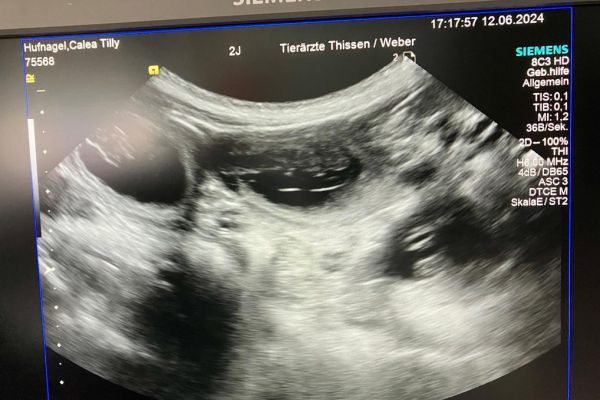

Good News. Tilly hat bereits vor einer Woche ihr süßes Geheimnis gelüftet und gestern haben wir auch bei Stinas Ultraschall einige kleine blinde Passagiere gesehen.